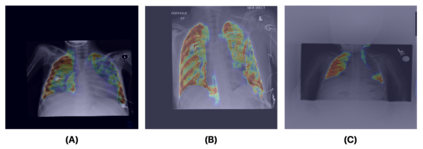

Medical image analysis continues to hold interesting challenges given the subtle characteristics of certain diseases and the significant overlap in appearance between diseases. In this work, we explore the concept of self-attention for tackling such subtleties in and between diseases. To this end, we introduce MEDUSA, a multi-scale encoder-decoder self-attention mechanism tailored for medical image analysis. While self-attention deep convolutional neural network architectures in existing literature center around the notion of multiple isolated lightweight attention mechanisms with limited individual capacities being incorporated at different points in the network architecture, MEDUSA takes a significant departure from this notion by possessing a single, unified self-attention mechanism with significantly higher capacity with multiple attention heads feeding into different scales in the network architecture. To the best of the authors' knowledge, this is the first "single body, multi-scale heads" realization of self-attention and enables explicit global context amongst selective attention at different levels of representational abstractions while still enabling differing local attention context at individual levels of abstractions. With MEDUSA, we obtain state-of-the-art performance on multiple challenging medical image analysis benchmarks including COVIDx, RSNA RICORD, and RSNA Pneumonia Challenge when compared to previous work. Our MEDUSA model is publicly available.